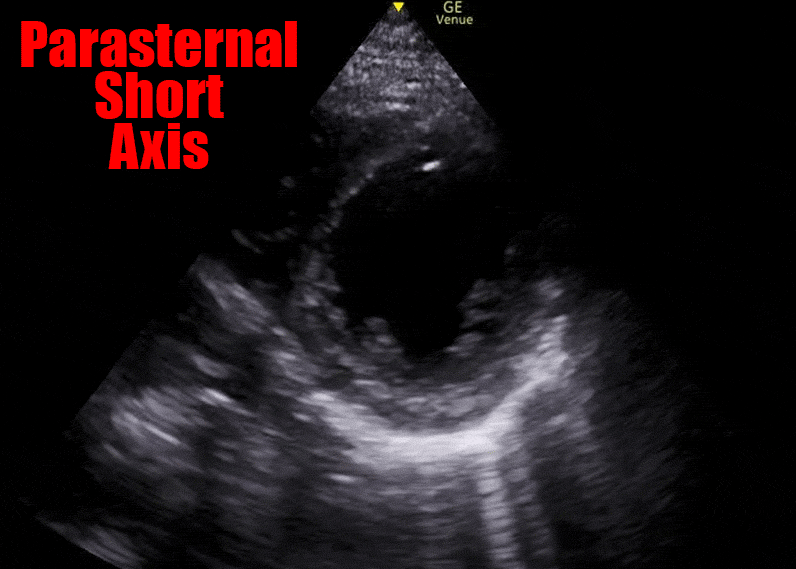

In a normal heart, the muscle of the left ventricle will contract and all segments will move toward an imaginary center point. It should look like the following image: